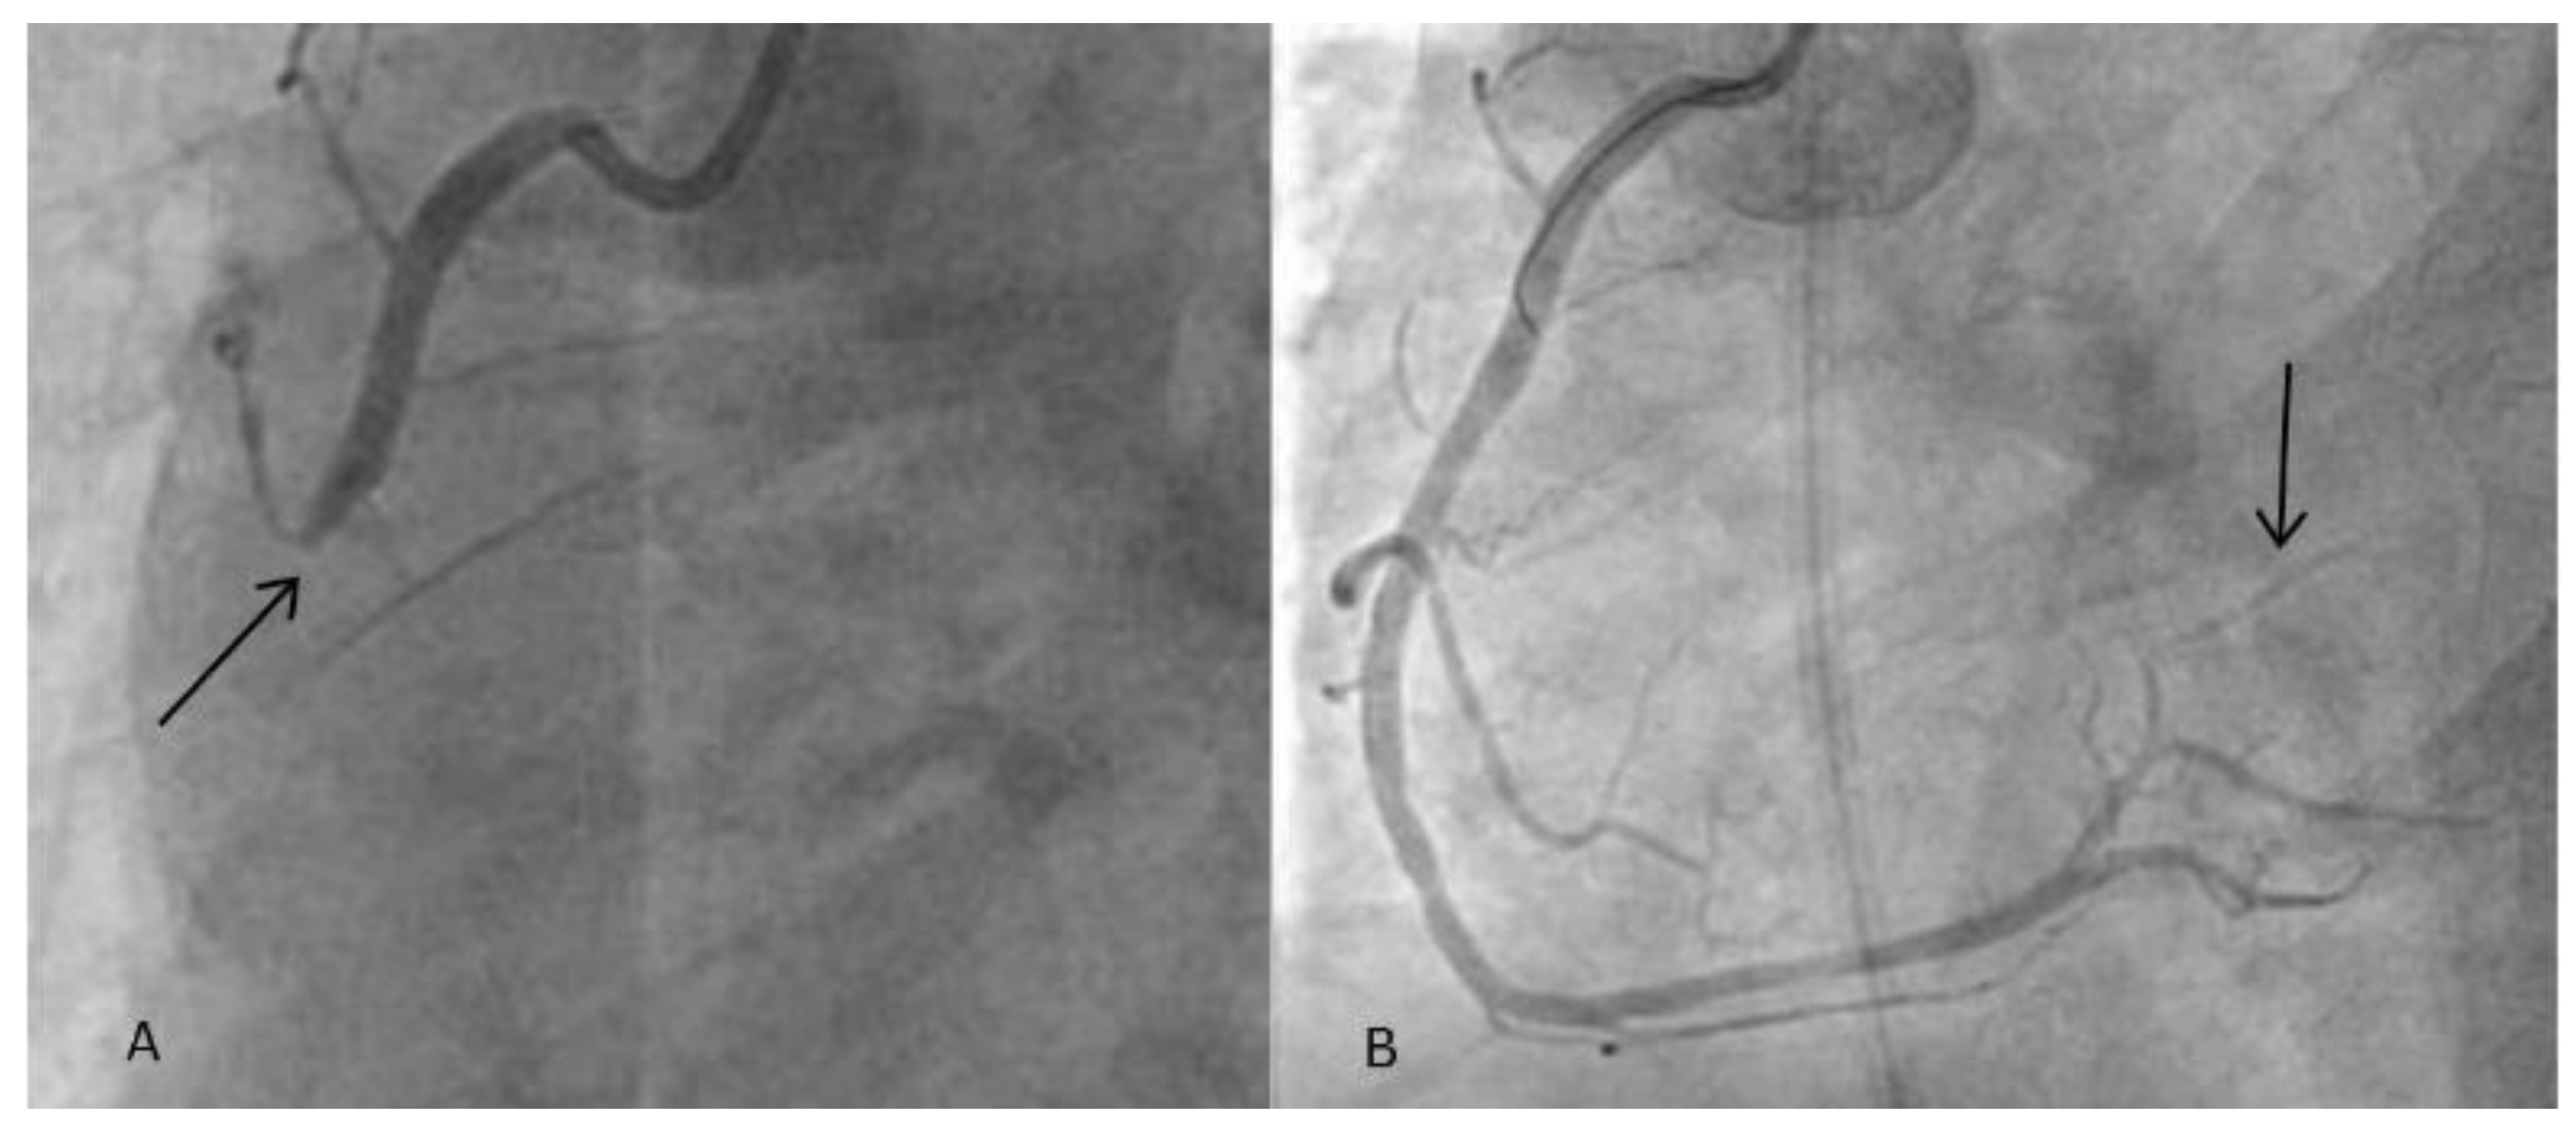

The coronarangiography confirmed an inferior wall STEMI due to a thrombotic occlusion of the mid-right coronary artery (RCA) (Figure 1A). Figure 1B shows the final angiographic result after balloon angioplasty and stenting with a single drug-eluting stent, with subsequent reperfusion of the AV nodal artery.

Figure 1. (A): Coronarangiography of the RCA showing thrombotic occlusion of the vertical segment (arrow). (B): Coronarangiography after balloon angioplasty and stenting of the mid-RCA, showing TIMI III flow and reperfusion of the AV nodal artery (arrow). PCI: percutaneous coronary intervention. RCA: right coronary artery. AV: atrioventricular.